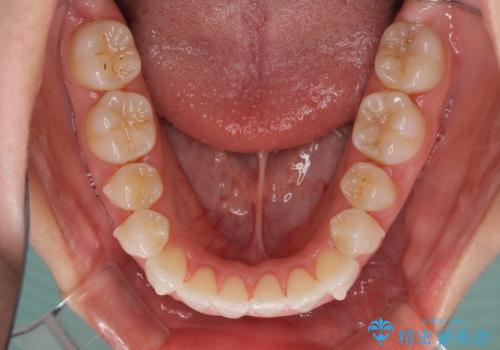

- 前歯のデコボコとクロスバイトを治したいとのことで来院された患者様です。

上下顎ともに歯列全体の側方拡大とIPR(歯と歯の間を削る)によってデコボコとクロスバイトが解消するように設計し、インビザラインにより治療を行うこととしました。

下顎骨の左側への骨格的なずれが強く、上下の正中の位置合わせや奥歯の咬み合わせ構築に苦労しました。